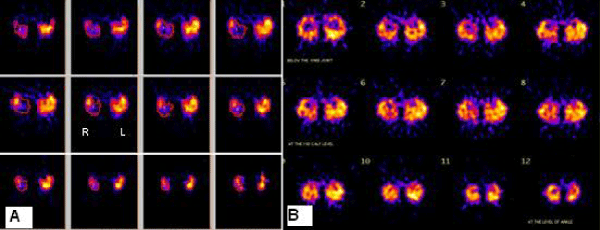

| Figure 3: a)Reconstructed Short Axis Slices of 99mTc-MIBI SPECT of Patient showing the Lack of Perfusion of the Posterior Compartment of Right Leg (Viewers Left) and Normal Perfusion in the Left Leg (viewers right). b) Follow up 99mTcTc MIBI SPECT Reconstructed Short Axis Slices of Patient Show Moderate Improvement in Perfusion Status of Right Limb. |